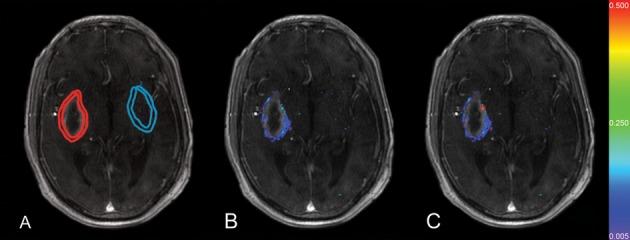

METHODS AND RESULTS

Twenty-five prospectively enrolled patients from the Diagnostic Accuracy of MRI in Spontaneous intracerebral Hemorrhage (DASH) study were examined using DCE MRI at 1 week after symptom onset. Contrast agent dynamics in the brain tissue and general tracer kinetic modeling were used to estimate the forward leakage rate (K(trans)) in regions of interest (ROI) in and surrounding the hematoma and in contralateral mirror-image locations (control ROI). In all patients BBB permeability was significantly increased in the brain tissue immediately adjacent to the hematoma, that is, the hematoma rim, compared to the contralateral mirror ROI (P<0.0001). Large hematomas (>30 mL) had higher K(trans) values than small hematomas (P<0.005). K(trans) values of lobar hemorrhages were significantly higher than the K(trans) values of deep hemorrhages (P<0.005), independent of hematoma volume. Higher K(trans) values were associated with larger edema volumes.

CONCLUSIONS

BBB leakage in the brain tissue immediately bordering the hematoma can be measured and quantified by DCE MRI in human ICH. BBB leakage at 1 week is greater in larger hematomas as well as in hematomas in lobar locations and is associated with larger edema volumes.

前瞻性纳入来自自发性脑出血的 MRI 诊断准确性研究(DASH)的 25 例患者,在发病后 1 周进行 DCE MRI 检查。使用对比剂在脑组织中的动力学和一般示踪剂动力学模型,估计 ROI 内和周围的正向漏出率(K(trans)),以及血肿对侧镜像 ROI(对照 ROI)。在所有患者中,与对侧镜像 ROI 相比,紧邻血肿的脑组织(即血肿边缘)的 BBB 通透性明显增加(P<0.0001)。大血肿(>30 mL)的 K(trans)值高于小血肿(P<0.005)。与深部出血相比,叶状出血的 K(trans)值明显更高(P<0.005),而与血肿体积无关。较高的 K(trans)值与更大的水肿体积相关。

结论

DCE MRI 可测量和量化人类 ICH 紧邻血肿的脑组织中的 BBB 渗漏。较大的血肿以及叶状位置的血肿在 1 周时的 BBB 渗漏更大,与更大的水肿体积相关。